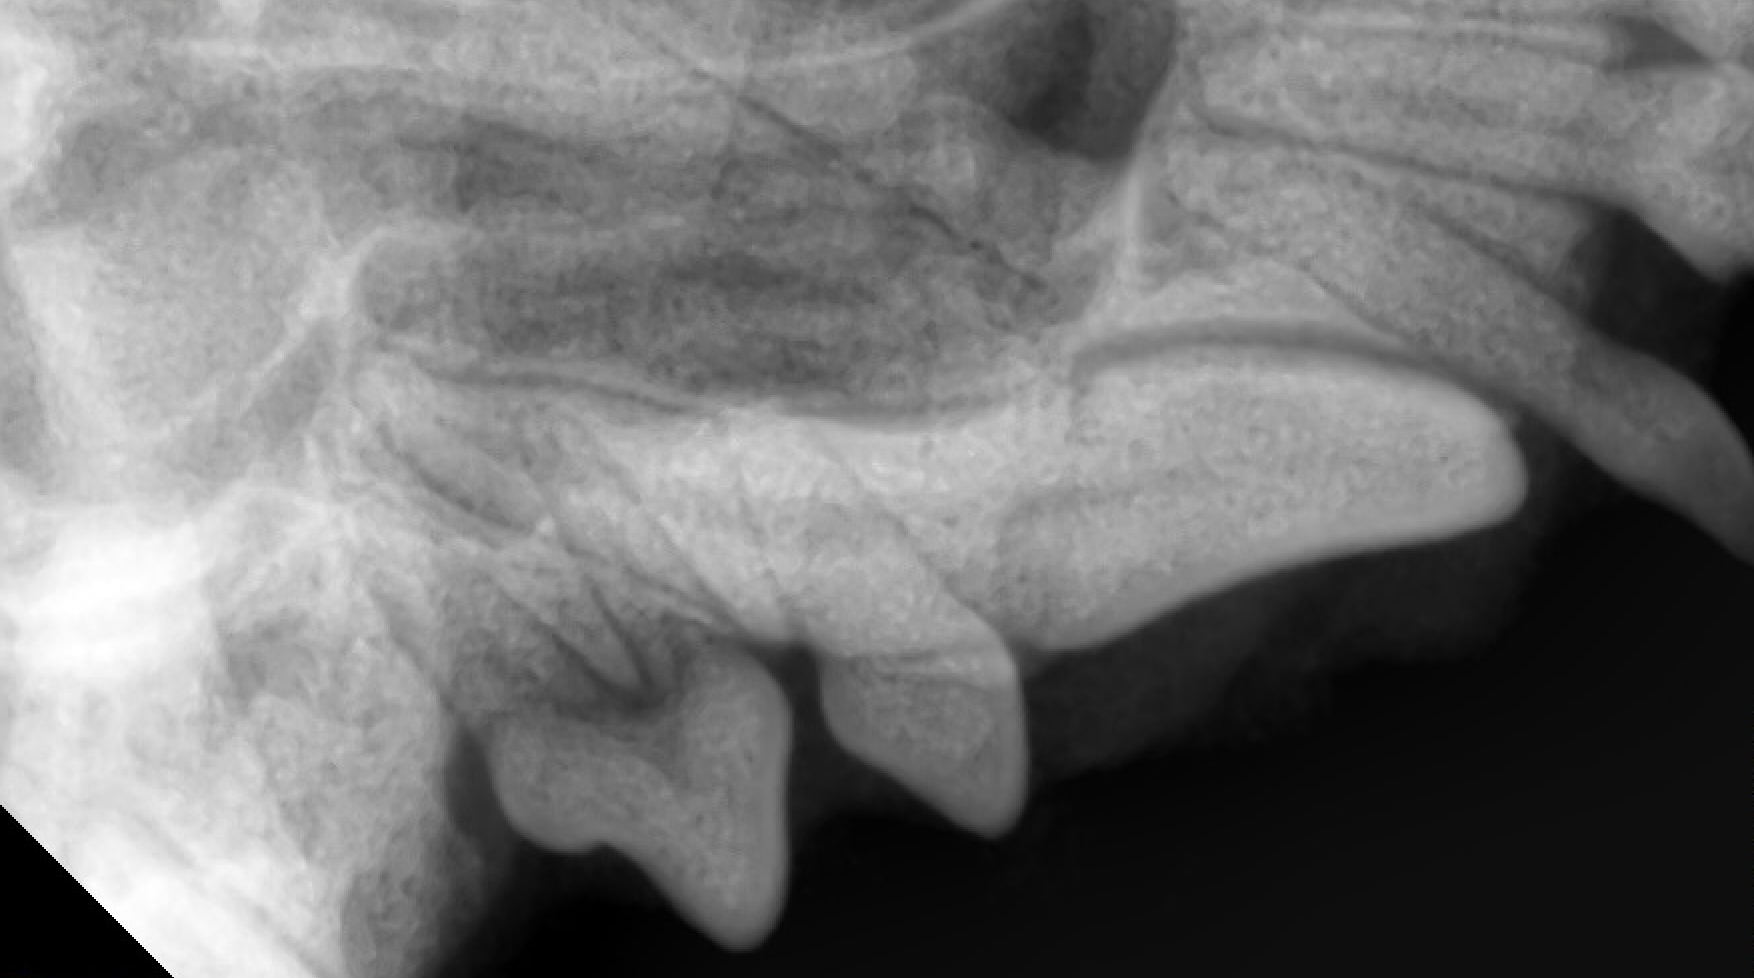

抜歯後、残った歯の一部がないか歯科レントゲン検査も実施します。

半年後に再度検査を実施しました。

抜歯した場所での嚢胞形成はなく、上顎の骨が新たに形成されていました。